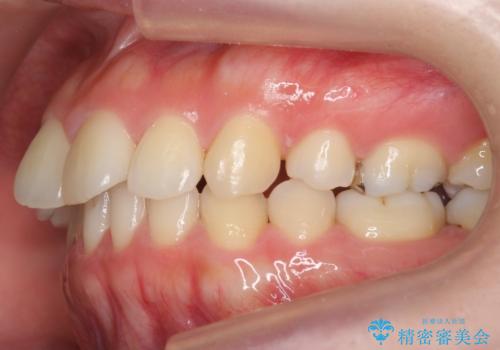

再矯正 昔ワイヤーで治療 前歯の並びを再度きれいに

- 小さいころに小臼歯を抜歯しワイヤー矯正をしたが、すき間が空いてきて、前歯の並びが戻ってしまったとのこと。

インビザラインライトという部分矯正コースで、全体矯正に比べ、比較的安価に治療しました。

前歯の並びが格段にきれいになり、大変喜んでいただけました。